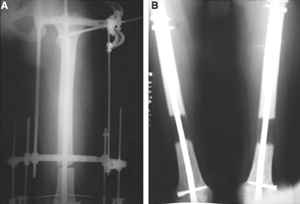

Разрешите рассказать о пациенте, которому мы фиксировали перелом такой конструкцией.

Больной 19 ти лет, пострадал в результате ДТП, пассажир мотоцикла. Получил открытый оскольчатый перелом н/3 левой бедренной кости 3a тип по Гастилло-Андерсену. При поступлении ПХО ран, фиксация стержневым аппаратом наружной фиксации. Лечение больного осложнилось развитием анаэробной флегмоны левого бедра. Лампасные разрезы, неоднократные некрэктомии, некротизировался участок диафиза левой бедренной кости на протяжении 15 см. Произведена резекция. 20.05.10- демонтаж АНФ, остеоситез левой бедренной кости гибридным циркулярно-монолатеральным стержневым дистракционным аппаратом наружной фиксации, остетомия левой бедренной кости в в/3. Сейчас начата дистракция в аппарате, проводится подготовка ран к аутодермопастике.

С уважением. Удачи!

5.jpg